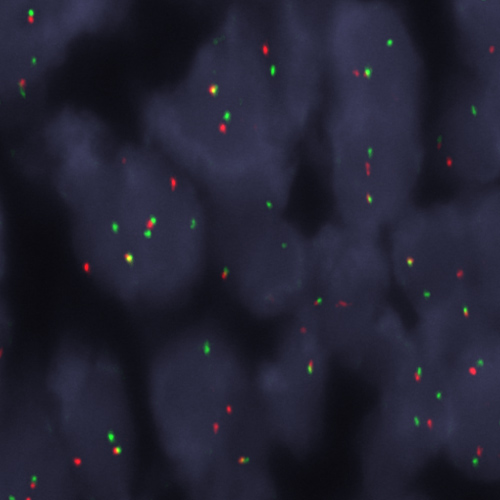

Ewing Sarcoma stained using EWSR1 (22q12) Break – XL for BOND (KBI-XL019).

The EWSR1 (22q12) Break - XL for BOND FISH probe detects genomic translocations involving the EWSR1 gene in FFPE tissues. EWSR1 (22q12) Proximal - XL and EWSR1 (22q12) Distal - XL are optimized to detect genomic regions proximal and distal to break points in the EWSR1 gene region.

When combined, both probes are used to detect translocations involving the EWSR1 gene at 22q12.